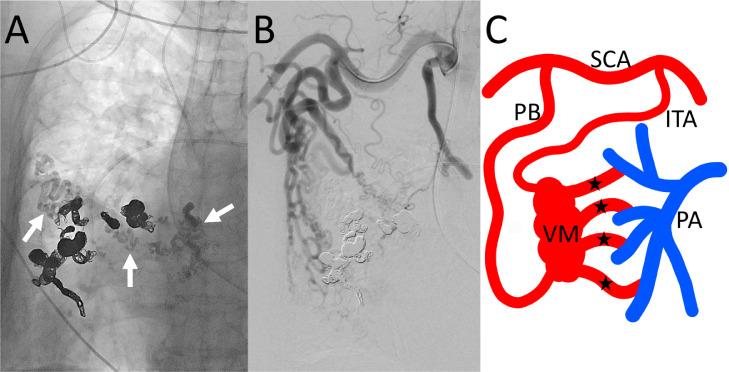

A 74-year-old woman presented with progressive dyspnea. Computed tomography revealed a large systemic artery-to-pulmonary artery vascular malformation (VM) on the right chest wall. Embolization of the VM was performed. First, the main drainers of the VM were retrogradely selected from the segmental pulmonary arteries and embolized using microcoils. Second, 2 main feeders of the VM were selected and embolized with N-butyl cyanoacrylate. Thus, marked flow reduction in the VM was achieved, and the patient's symptom improved dramatically. We believe that embolization of both feeders and drainers is an effective technique for treatment of a chest wall systemic artery-to-pulmonary artery VM.

摘要

一名74岁女性因进行性呼吸困难就诊。计算机断层扫描显示右胸壁存在一个大型体动脉至肺动脉血管畸形(VM)。对该VM进行了栓塞治疗。首先,从肺段动脉逆行选择VM的主要引流血管,并用微线圈进行栓塞。其次,选择VM的2条主要供血血管,用氰基丙烯酸正丁酯进行栓塞。由此,VM内的血流显著减少,患者症状明显改善。我们认为,对供血血管和引流血管同时进行栓塞是治疗胸壁体动脉至肺动脉VM的有效技术。